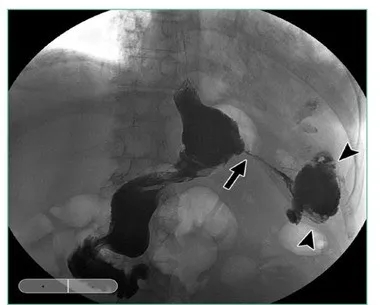

图上显示胃底切割线交叉处是瘘发生部位,

瘘发生的最常见部位

在袖管胃上三分之一地方,

由于袖管胃缩窄或狭窄,

导致胃内爆破压升高,

在靠近食管胃结合部附近的

袖管胃缝钉线上,因这里相对比较薄弱,

容易发生破裂而形成瘘。